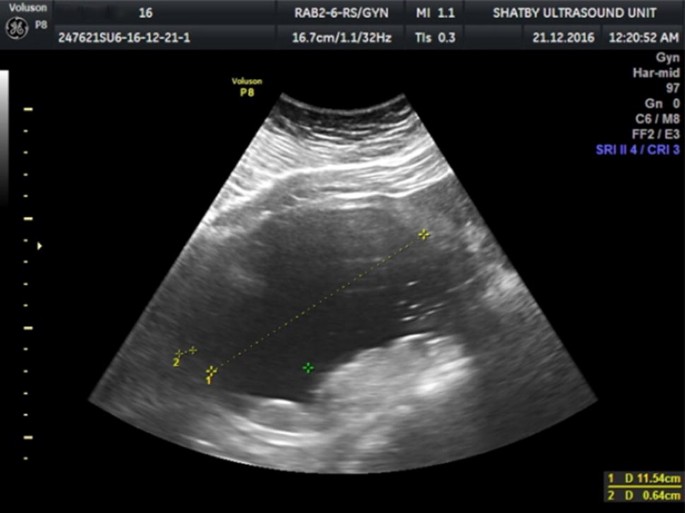

View Adnexal Mass Ultrasound Background. Adnexal masses are usually diagnosed by a pelvic exam, ultrasound, or both. An adnexal mass is a lump in tissue of the adnexa of uterus.

Characterisation of an adnexal mass. Causes of adnexal mass in post menopausal women. Ancillary findings and clinical correlates.

Ancillary findings and clinical correlates. Adnexal masses can be benign or cancerous, and they can be categorized as simple or complex. Although ultrasound has so far been found to be ineffective as a screening tool for ovarian cancer, it is commonly used as a means of evaluating or following ovarian or adnexal masses once they are. The benefit of ultrasound is the characterization of an adnexal mass, suggesting the probable etiology of the mass.